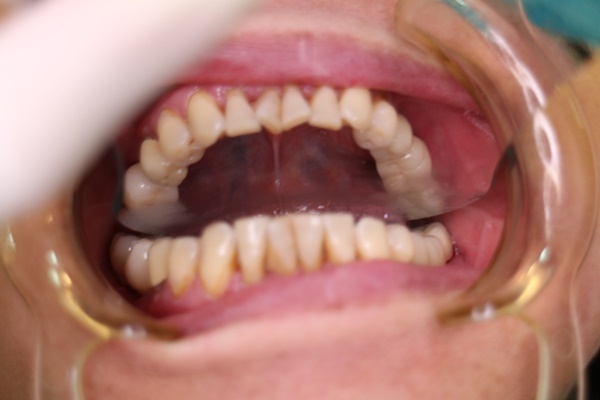

真正在台中植牙之前,會經過這幾次牙齒治療,畢竟像吳立琳醫師這種良醫不可能隨便鑽個洞直接植牙進去收工。正確來說都會先處理你口腔內現有的狀況,例如蛀牙、牙周病…等等諸如此類,反正就是先把疑難雜症處理完,再來好好植牙。

回歸我的口腔,原本就有牙周病,加上缺牙不補,我好幾顆牙齒就是因為沒有即時來找吳立琳醫師,導致原本留得住的地方,現在早就掉光光。